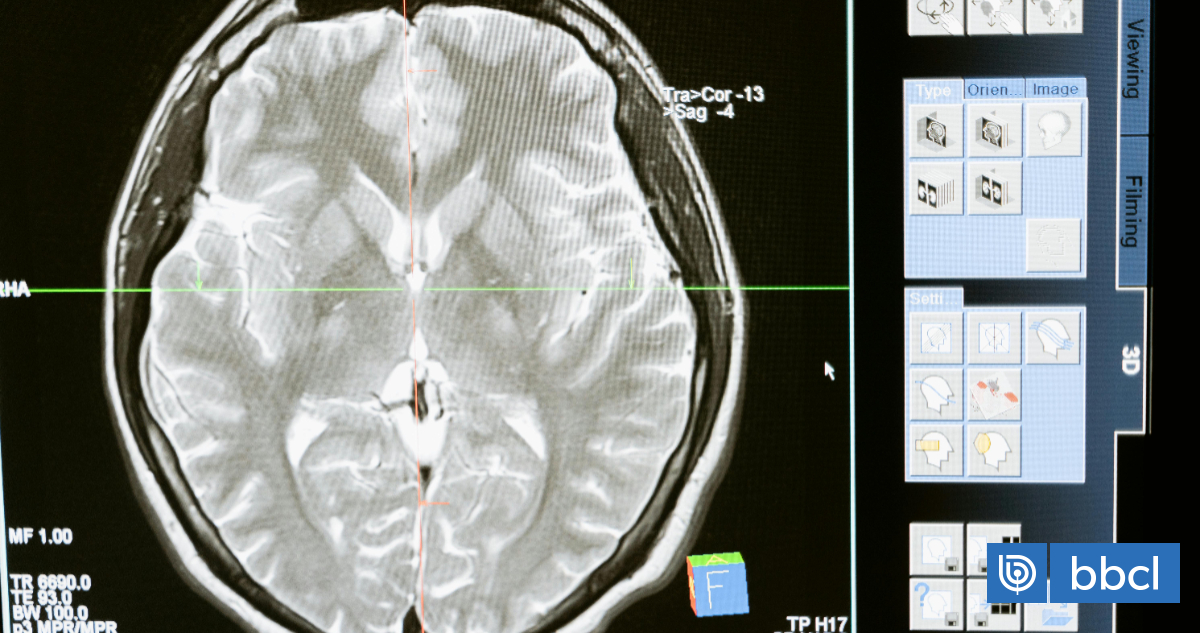

Para mapear este envejecimiento, los científicos utilizaron modelos de aprendizaje automático entrenados con escáneres cerebrales obtenidos del Biobanco del Reino Unido de 15.334 participantes sanos, para medir la diferencia entre la edad cerebral predicha de un individuo y su edad real, conocida como brecha de edad cerebral.

Este modelo se utilizó posteriormente para analizar dos resonancias magnéticas cerebrales de 996 participantes sanos, tomadas con al menos dos años de diferencia. En el grupo control (564 individuos), ambos escáneres se realizaron antes de la pandemia, y en el grupo “pandemia” (432 individuos), un escáner se realizó antes y otro después del inicio de la misma.